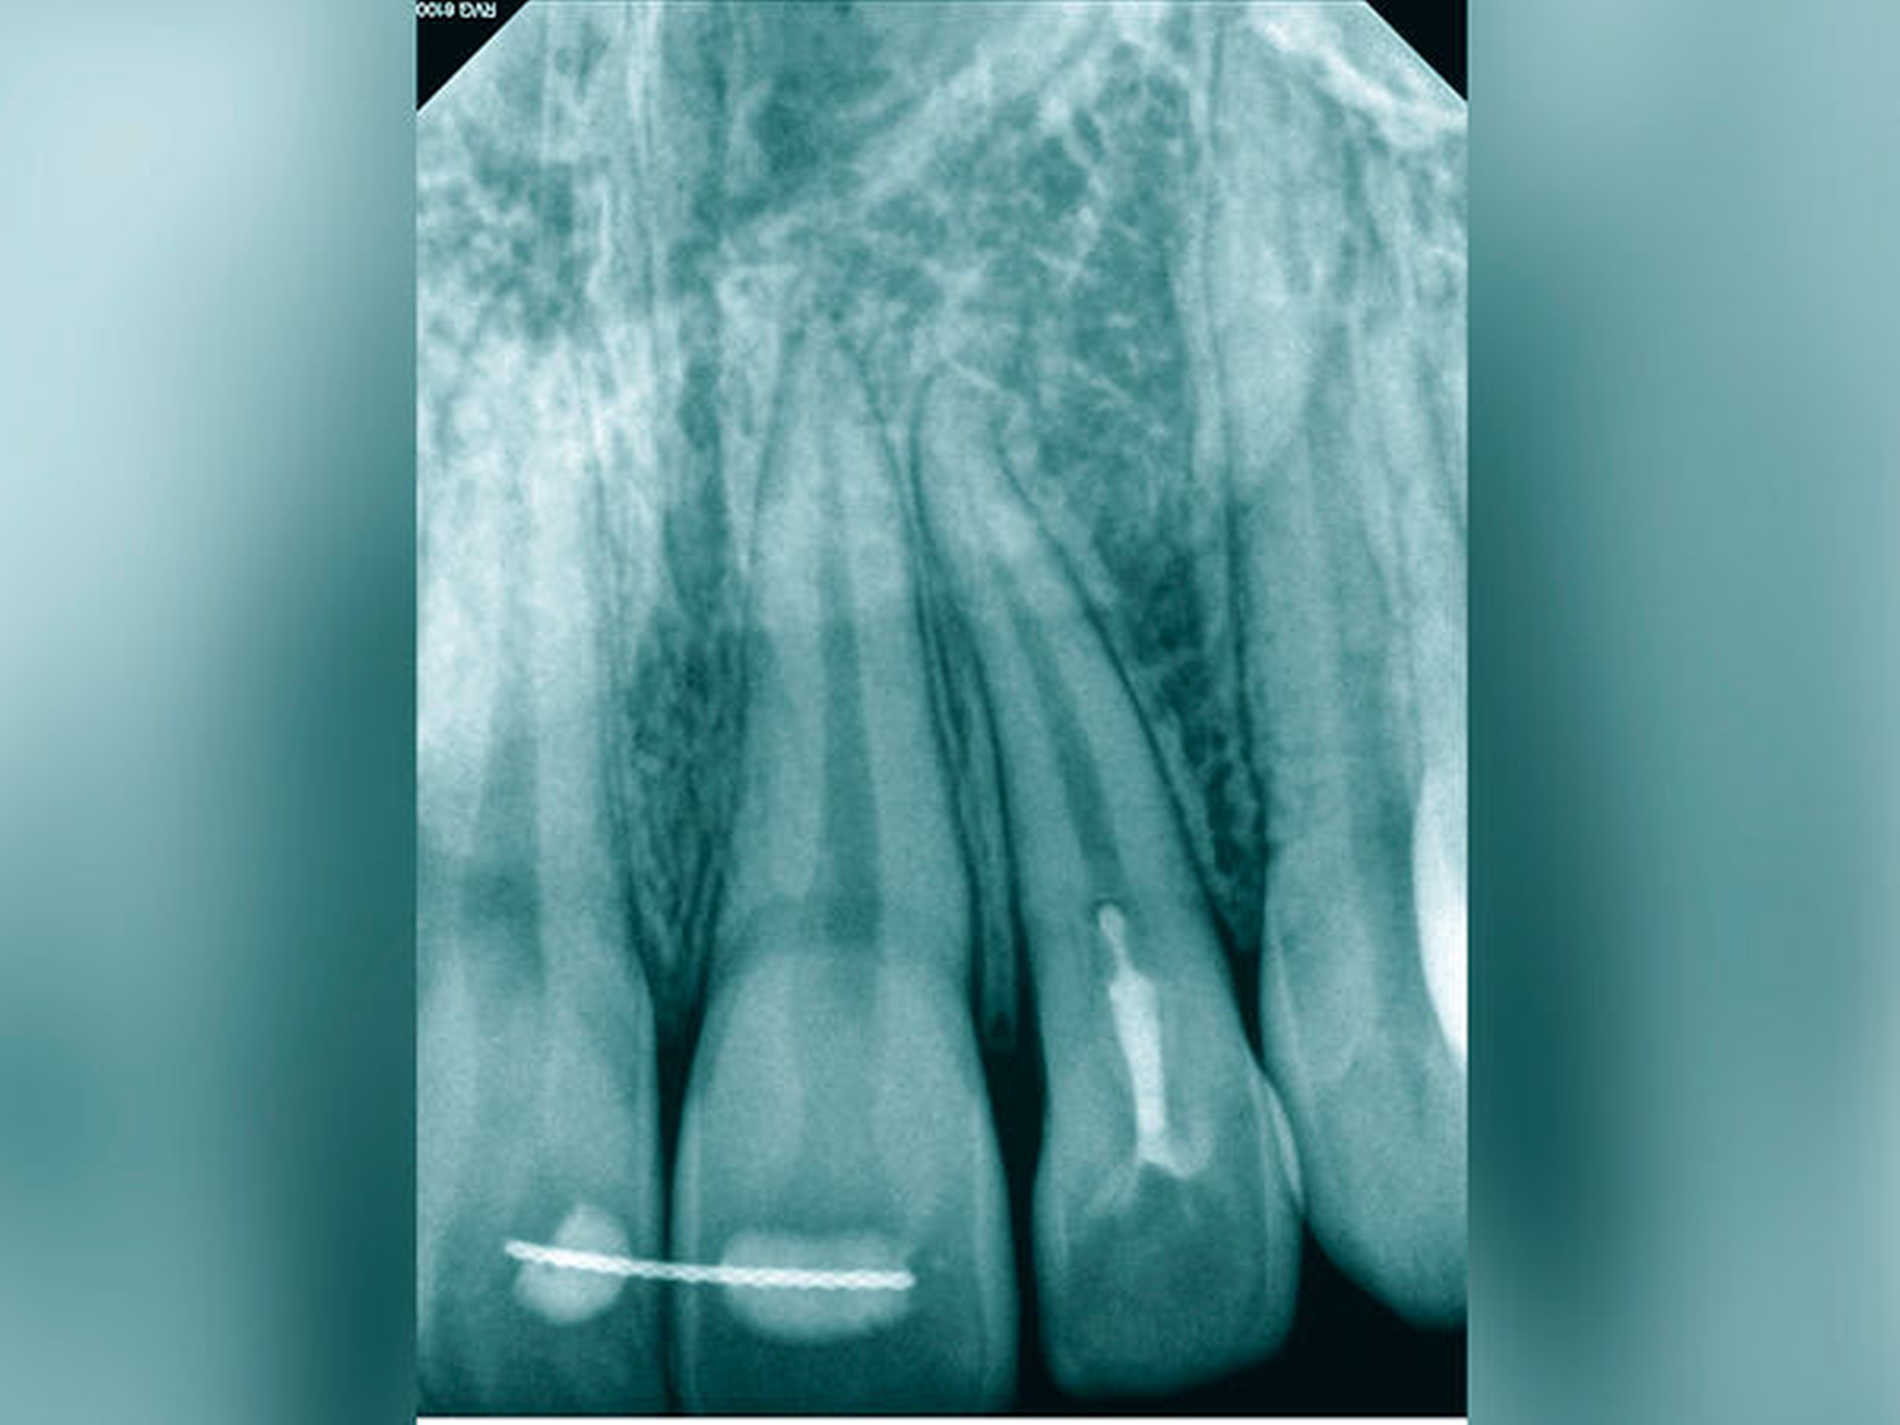

Der Schwierigkeitsgrad entspricht dem Grad II. Sowohl in der Diagnostik als auch in der Therapie liegen erhöhte Anforderungen vor. Der Allgemeinzustand, die verringerte Compliance, die eingeschränkte Mundöffnung und das erschwerte intraorale Röntgen ließen bereits im Verlauf der Befundaufnahme eine größere Schwierigkeit erkennen. Die Wurzelspitze ist stark nach mesial gekrümmt. Der sehr kleine Krümmungsradius kann eine Instrumentenfraktur begünstigen. Die Bedingungen für einen aseptischen Zugang unter Kofferdam lagen nicht vor, so dass vorbereitend eine Kariesentfernung und eine dentinadhäsive präendodontische Restauration erforderlich wurden (Abbildungen 13a und 13b).

Im Verlauf der IKD bestätigte sich eine partielle Pulpanekrose mit teilweise noch durchblutetem Pulpagewebe. Die Wurzelkanalbehandlung erfolgte mehrzeitig unter Verwendung von rotierenden NiTi-Instrumenten, der Wurzelkanal konnte so vollständig verschlossen werden (Abbildung 13c). Die Prognose aus endodontischer Sicht ist gut. Eine postendodontische Versorgung mit chirurgischer Kronenverlängerung ist zur langfristigen Sicherung des Erfolgs erforderlich.